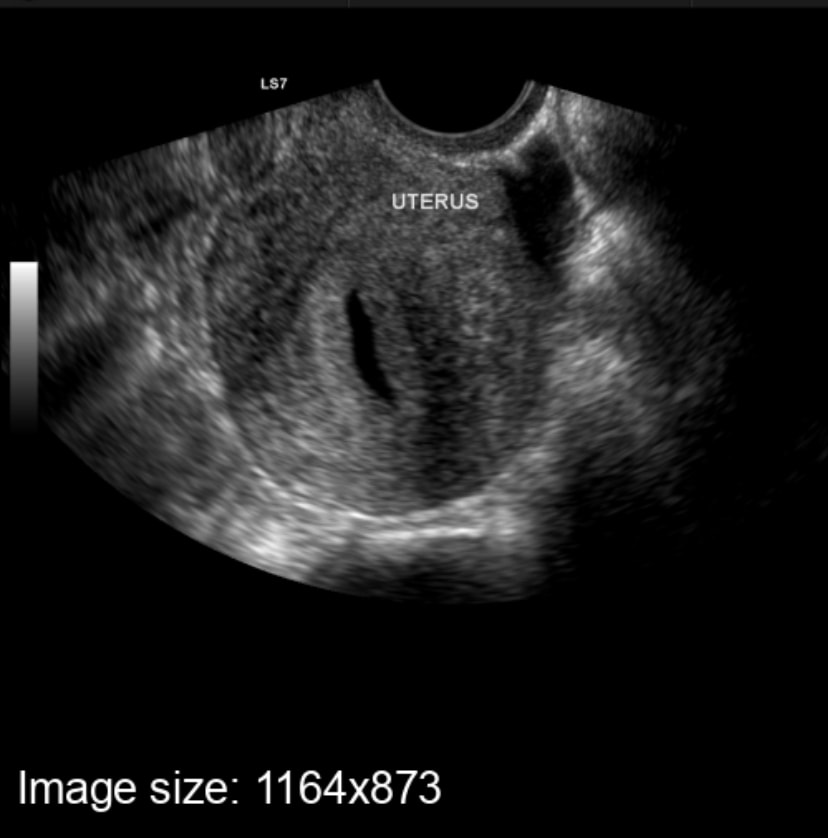

На УЗИ жидкость в матке! Положительный тест!

Всем здравствуйте ,задержка менструации уже 10 дней,тесты положительные,признаки беременности..вчера была ну УЗИ,врач не увидела плодного яйца в матке,но есть жидкость внутри матки,сказала что возможно зачатие только произошло.Но в интернете начиталась о том что так себя может проявить внематочная беременность(((девочки у кого было так ??рекомендовали сходить на УЗИ через 5 дней,что через это время должно быть все видно...Может кто то был в такой ситуации??очень извела себя,незнаю что уже думать,я в отчаянии..

У меня после прерывания матка плохо сократилась, видимо потому что срок большой, а ребёнка нет, не кормила грудью и естественный окситоцин не вырабатывается, искусственный не помог. И полость была расширена, в матке была жидкость, вот так же, как у вас на снимке. Я дополнительно колола окситоцин на 3 и 4 дц, но не помогло. Наступлению беременности не помешало, в 6 недель на снимке было еще видно эту расширенную полость и жидкость

И жидкость в матке не есть начало беременности

Галка, вообще врач сказала ,что буквально вчера была девушка с точно такой же проблемой через неделю то есть вчера ей сделали повторное УЗИ,и уже было видно нормальную маточную беременность.и что скорее всего через неделю мы увидим что все хорошо.и что скорее всего была поздняя овуляция и все только только началось развиваться.

Ольга, ну как поздняя овуляция, если у вас уже 10 дней тесты полосатят. Вам ниже Марина все правильно написала, что если отталкиваться от тестов, то у вас хгч уже за 1000 точно есть, а при таких значениях обычно пя уже видно

Ольга, с определением внематочной по узи все сложно, далеко не всегда видят.( У меня не видели, а по факту труба готова была лопнуть) Чаще всего ее диагностируют по косвенным признака. Хгч растёт (иногда лучше, иногда хуже), а ПЯ в матке не визуализируется. Совсем не обязательно, что это Ваш случай. Но пока ПЯ не видно в матке, при достаточно высоком хгч (или давно полосатых тестах) исключать ее нельзя.

Ольга, за 10 дней от первой еле видной полоски при хорошем росте хгч до тысячи дорастет,к примеру овуляция поздняя раз на первый д.з слабая полоска,ну может было 10-11 дпо,то через 10 дней уже 20-21 дпо и хгч от 1500 уже, жидкость меня тоже смущает

Вот Мой снимок